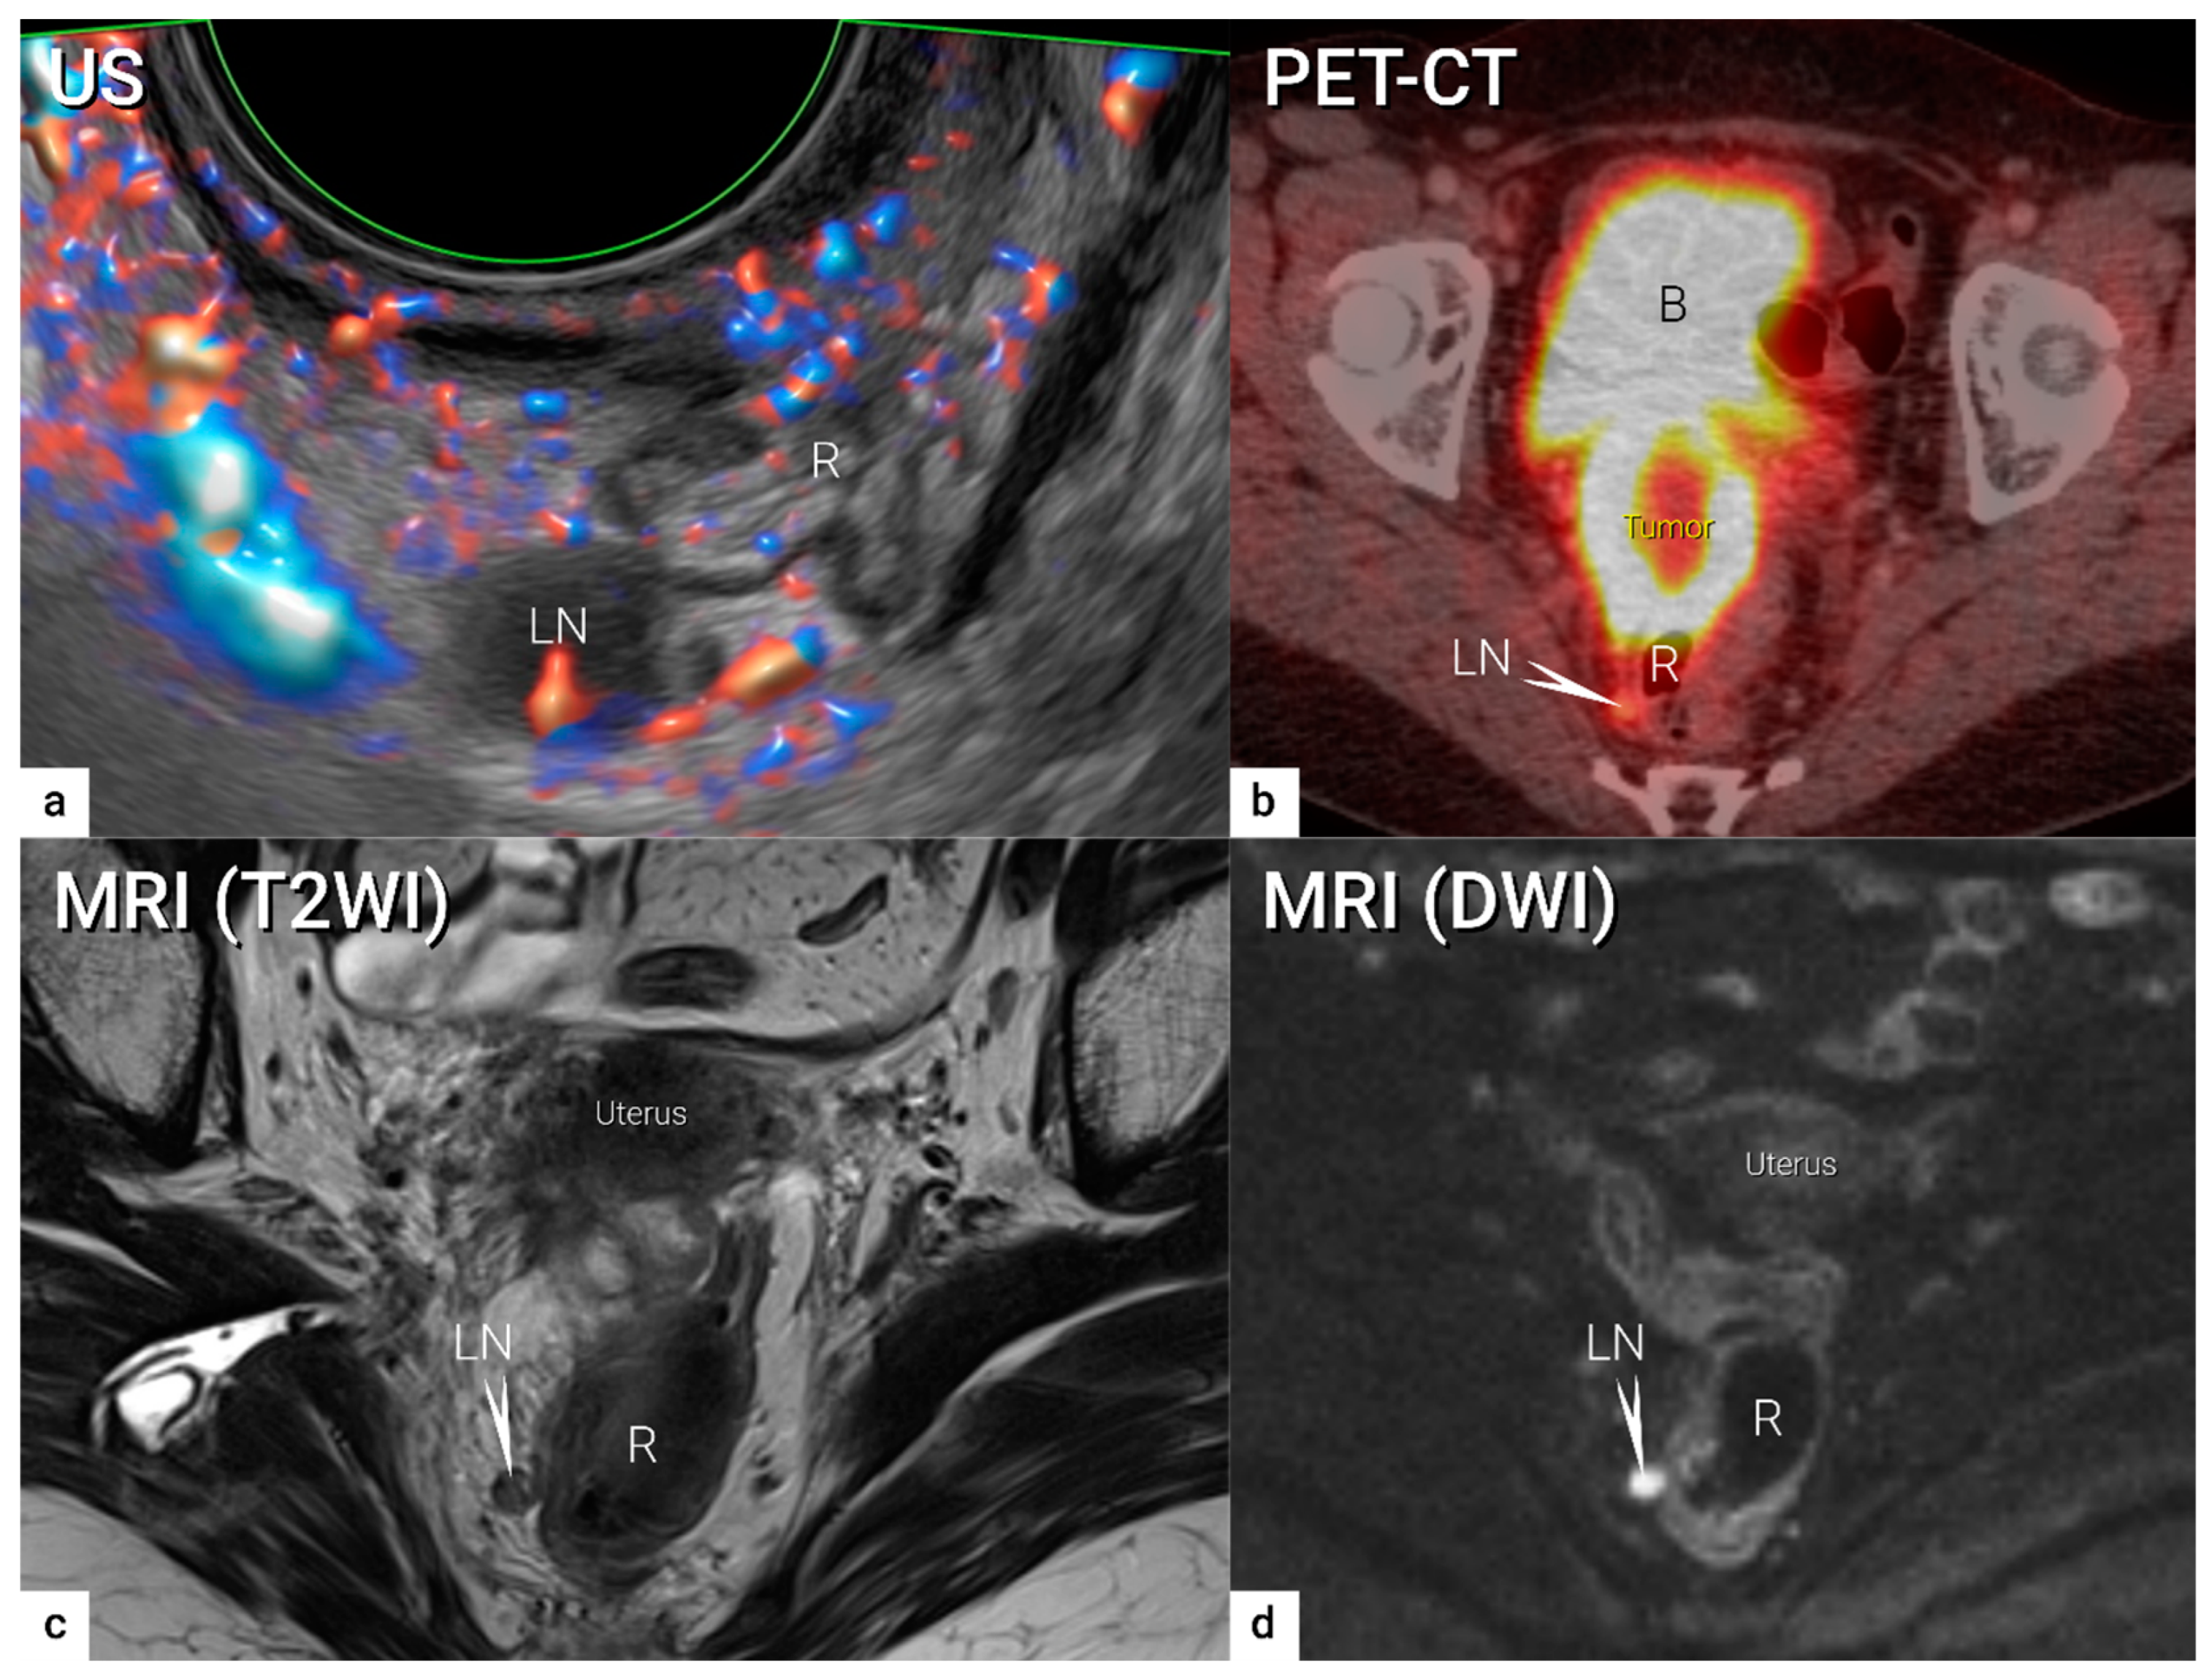

4. Nodal and Distant Diagnostic Workup

| N1 | IIIC1 | Regional lymph node metastasis to pelvic lymph nodes only | US: hypoechogenic rounded lymph node without preservation of typical architecture (loss of the nodal core-sign), inhomogeneous echogenicity due to cystic necrosis and calcifications, capsular interruption, grouping of metastatic lymph nodes and others. Hilar flow may still be preserved in a partial nodal involvement with or without transcapsular vascularisation (vessels penetrating the cortex from outside), the latter are usually found in an advanced stage of infiltration. MRI: lymph nodes with maximum transverse diameter >10 mm; capsule irregularity, rounded (as opposed to oval) shape, inhomogeneous signal with signs of necrosis on T2W images (MRI), restricted diffusion (DWI) or increased FDG-avidity (PET-CT) |